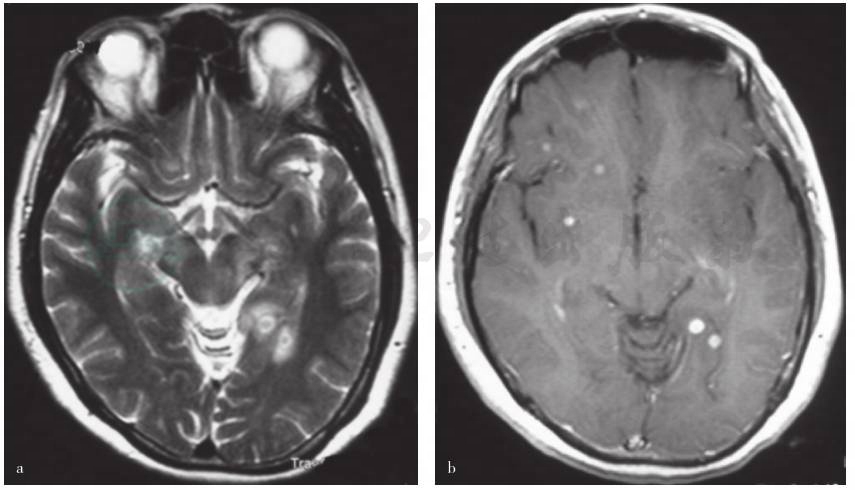

图1 头部CT和MRI检查所见

a.外院头部CT显示左侧外囊及顶叶条片状稍低密度影;b.外院头部MRI显示脑内多发异常信号